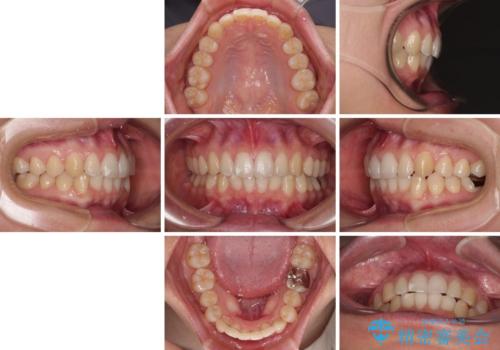

- 上下のクロスバイトと前歯のデコボコを気にして来院された患者様です。

インビザラインを用い、IPR(歯と歯の間を削る)と歯列全体を拡大させることで、歯並びを整えていくこととしました。

下の歯が隠れてしまうほどでしたが、深い咬み合わせも改善され、顎への負担も軽減されました。